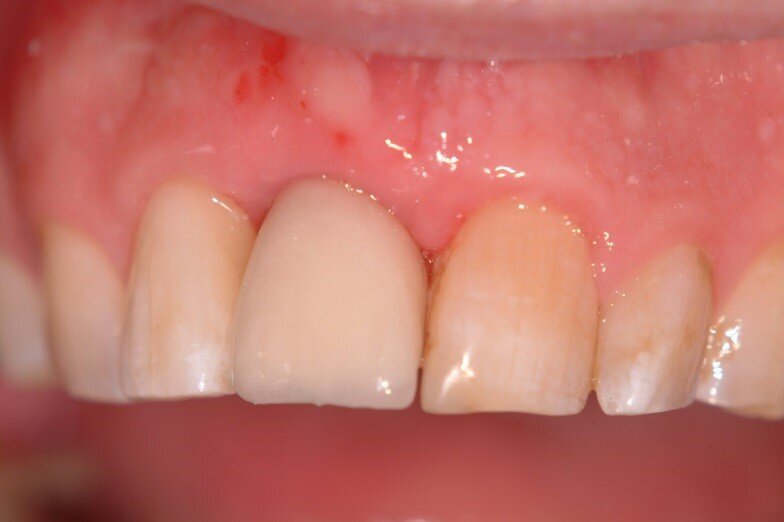

5. Bilateral pedicles using adjacent papilla to cover the connective tissue surfaces of the tuberosity graft (Fig. 5)

7. Monitoring of soft tissue healing. Tissue from the tuberosity and adjacent papillae gives a better match than palatal tissue. We are ready to re-enter when incision lines fully closed. (Fig. 6, 7)